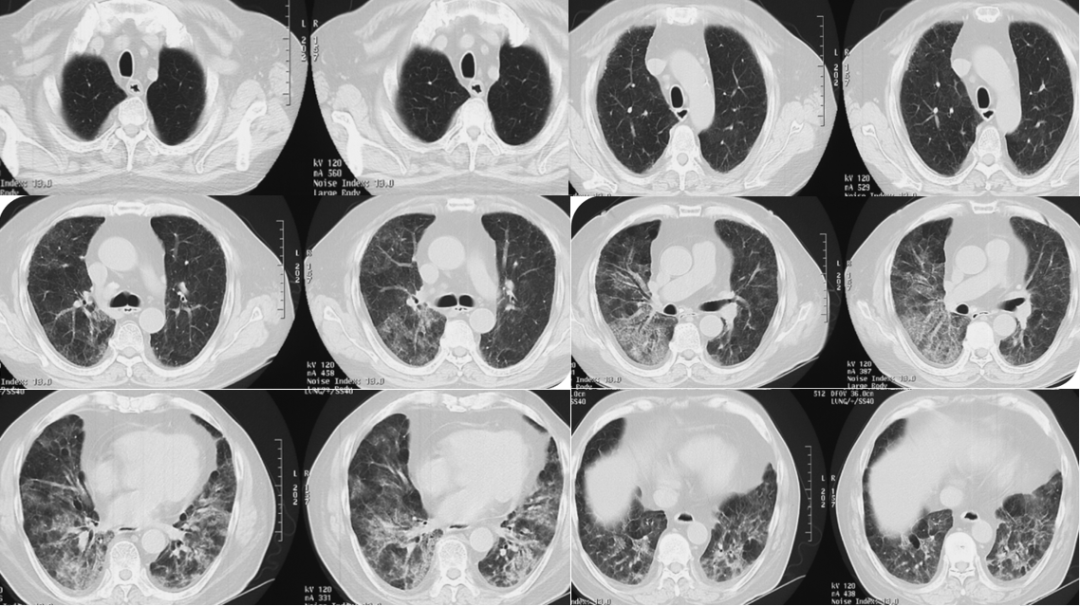

入院前2天(2021年1月22日)就诊于北京市普仁医院急诊科。血常规:WBC 9.1×109/L,NEU% 78.6%;凝血:D二聚体739 ng/ml(正常范围0~243 ng/ml),BNP 87 pg/ml(正常范围0~100 pg/ml)。胸部CT:双肺多发小叶间隔和小叶内间隔增厚,周围可见磨玻璃及网格影、结节、索条及少许实变,双肺呈“马赛克”样改变(图1)。予左氧氟沙星0.6 g qd、哌拉西林舒巴坦钠5g bid抗感染及赖氨匹林退热,并予吸氧(条件不详),患者症状无缓解。

图片

图1  患者胸部CT(2021-01-22,外院)